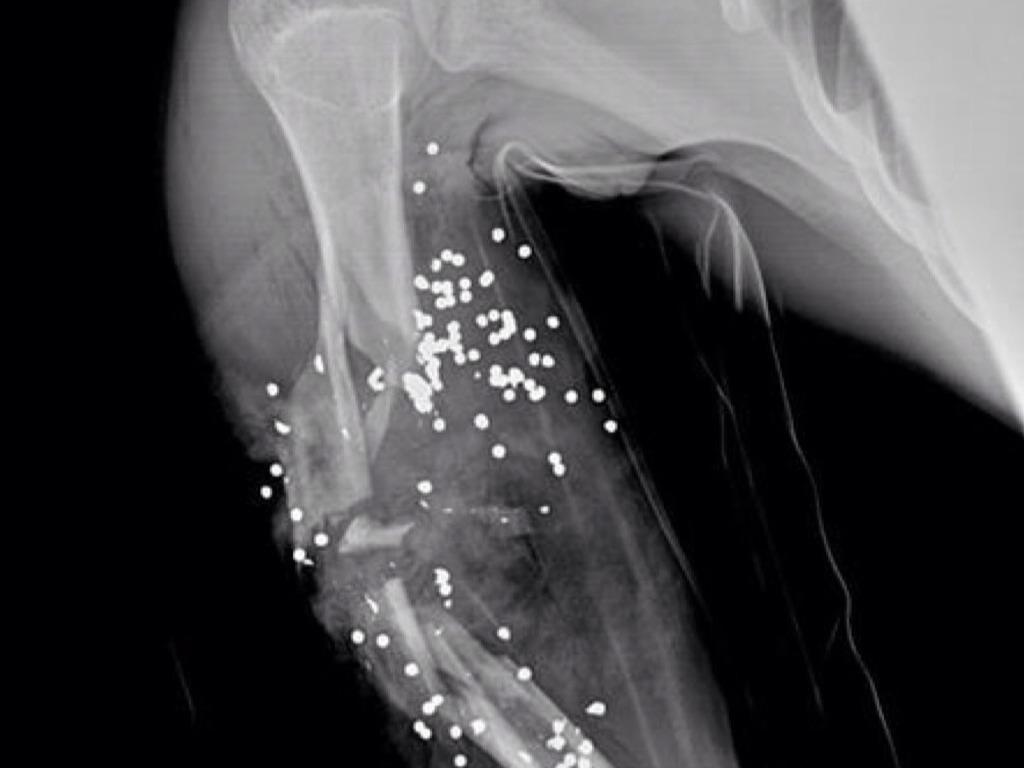

"young man was spear fishing"